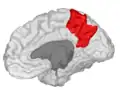

Precuneus

![]() Medial surface of left cerebral hemisphere. (Precuneus visible at top left.) (Anterior to the right.) | |

Precuneus of left cerebral hemisphere (shown in red). -

Medial surface of left cerebral hemisphere. (Precuneus visible at top left.) -

Medial surface of left cerebral hemisphere. (Precuneus colored in red.)